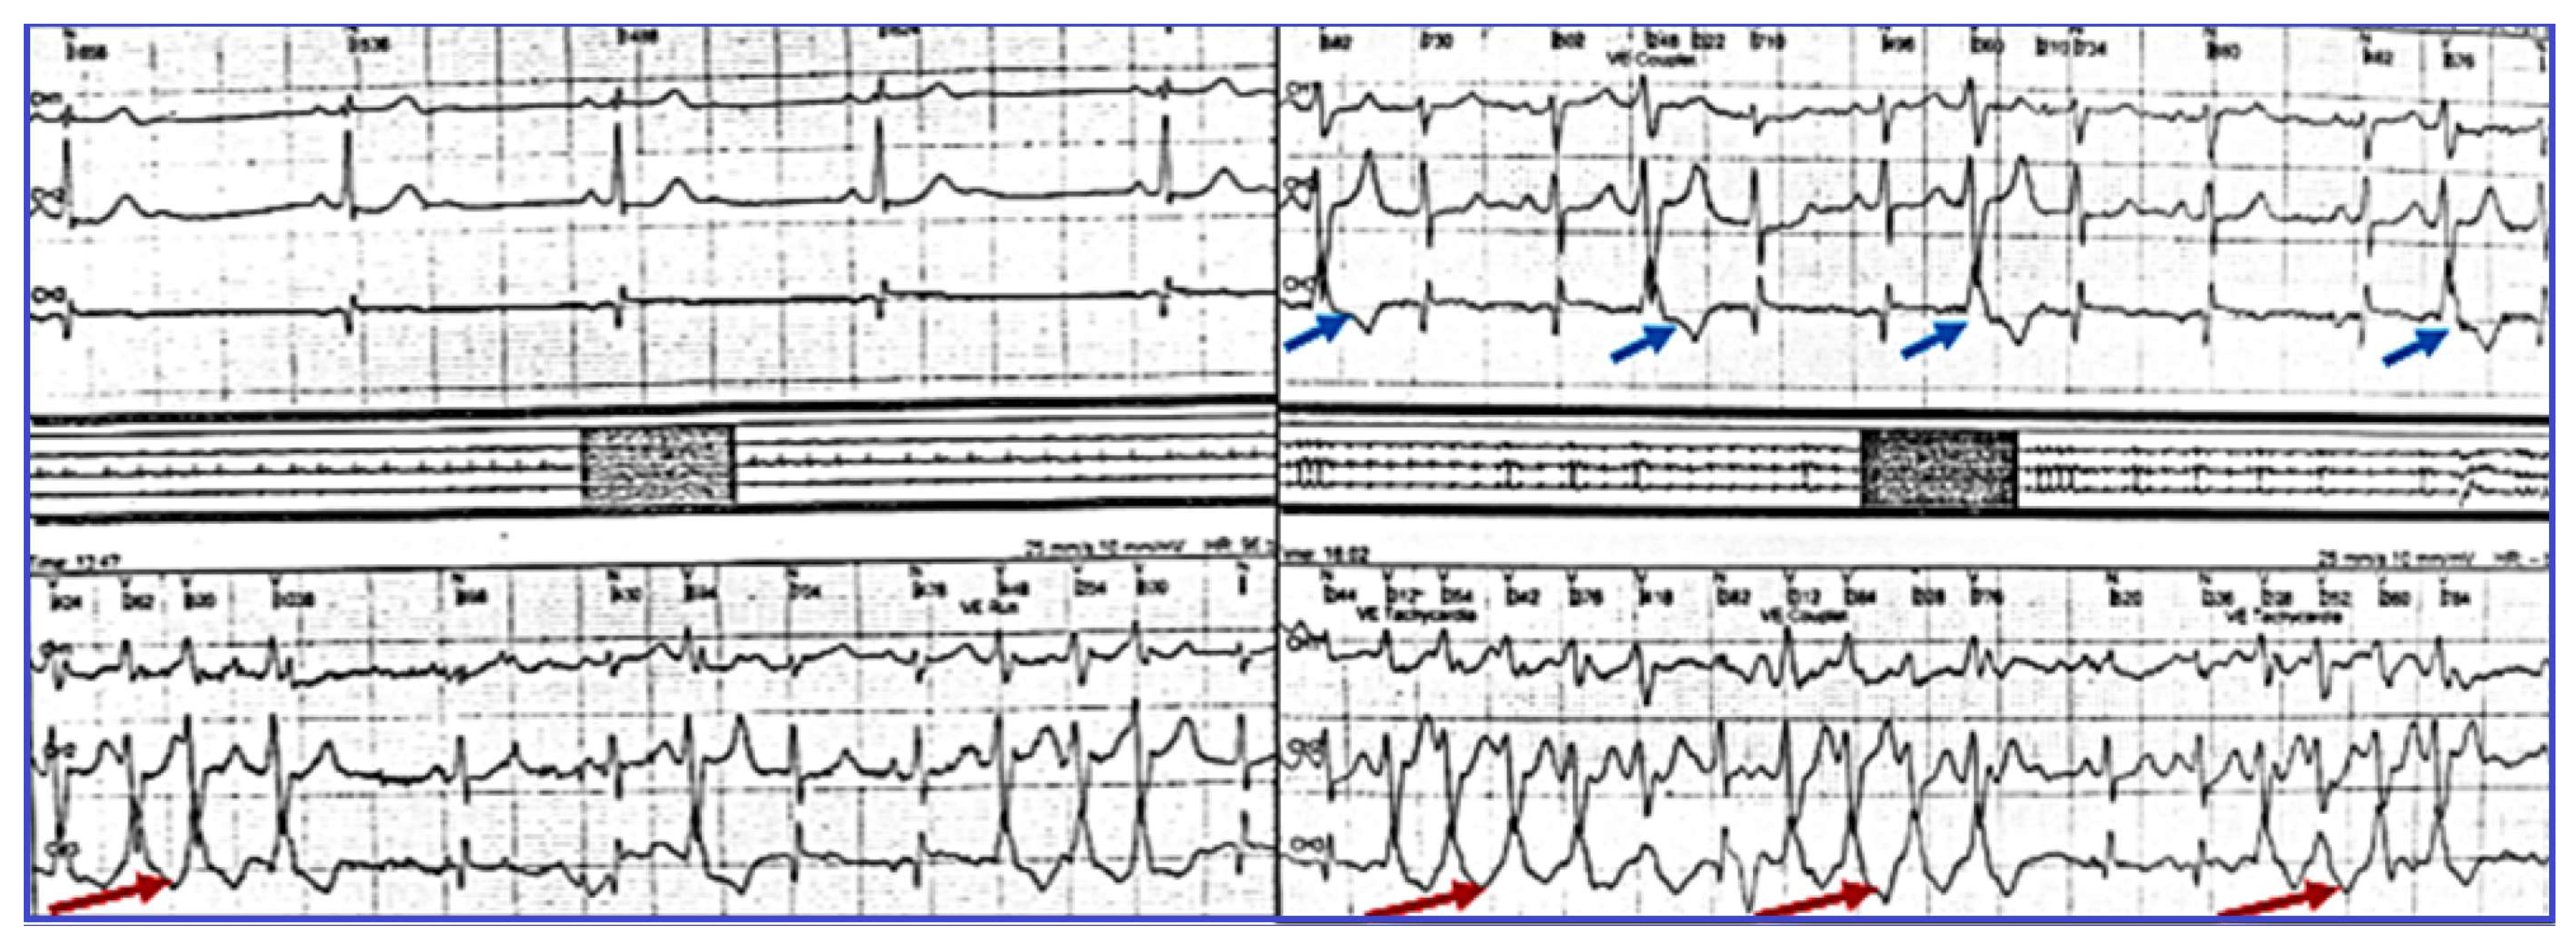

2.3. Evaluation of VA, Antiarrhythmic Therapy with Amiodarone and Secondary Effects